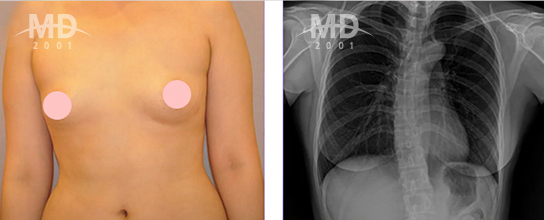

가슴재수술 전 검사

• 보형물 상태

(파열/변형)

• 피막 상태

(두께/위치)

• 피막 제거 여부

• 부작용 현황

• 유방암, 양성질환 진단

흉부 엑스레이 촬영

유방 정밀 촬영

유방초음파 검사

유방외과 전문의 유우상 유방검진센터장은 가슴재수술 전 총 5가지 검사를 통해

가슴상태를 정밀하게 진단하고, 검사 결과에 따라 알맞은 방법으로 재수술을 시행합니다. ※ 검사의 종류는 환자의 상태에 따라 달라질 수 있습니다.